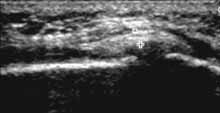

При этом в норме синовиальная оболочка не визуализируется. При деформирующем

остеоартрозе с синовитом отмечается увеличение сумки, выпрямление складок, наличие

избытка жидкости (Рис. 2). Жидкость относительно однородная. При воспалительном

Рис. 2. I стадия остеоартроза. Умеренное увеличение b. suprapatellaris

(1+) с наличием избытка относительно однородной жидкости, 2 — надколенник,

3 — бедренная кость.